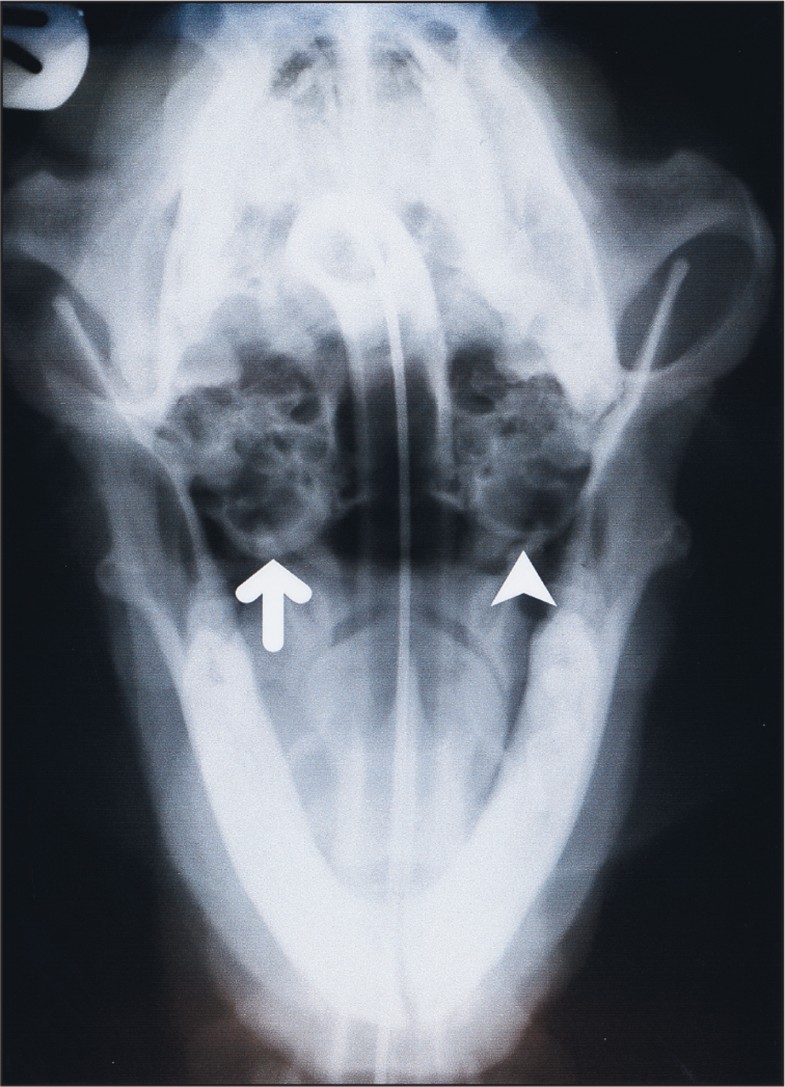

Surgical management of 43 cases of chronic otitis externa in the dog Dog Ear Infection Otitis Media Inflammation of the ear canal; learn about the causes, signs, diagnosis, and treatment of inflammation of the middle and inner ear in dogs. learn how ear infections (otitis) in dogs are caused by excess ear wax, bacteria, fungi, or allergies. otitis is divided into three types based on the location of a dog’s ear infection: Otitis interna. Dog Ear Infection Otitis Media.